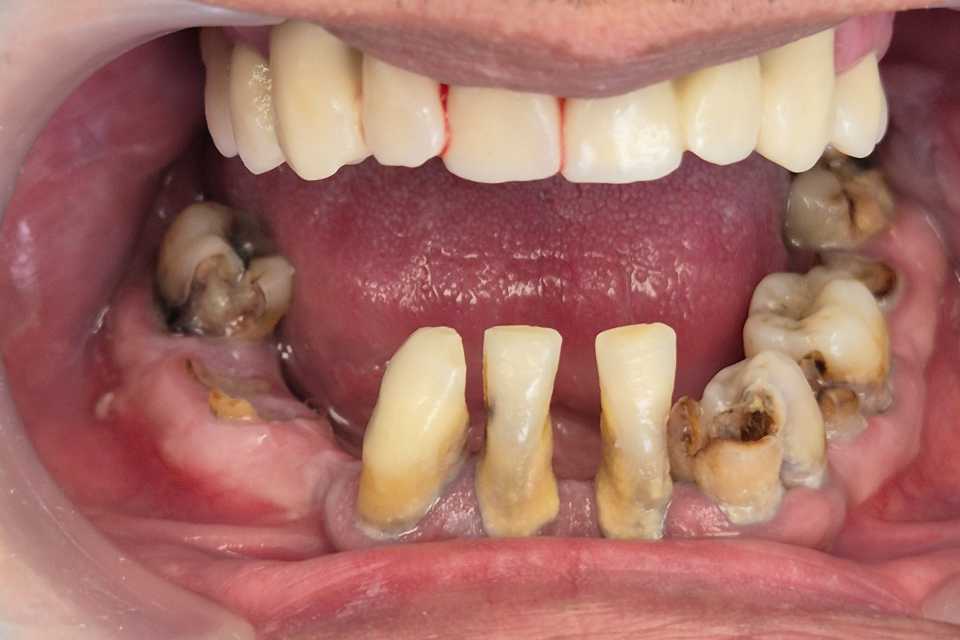

All on 6 protezate cu ajutoul unei lucrări din zirconiu pe suport de titan

All on 6 protezate cu ajutoul unei lucrări din zirconiu pe suport de titan.

Imaginile sunt prezentate în ordinea evoluției tratamentului, de la situația inițială la rezultatul final.